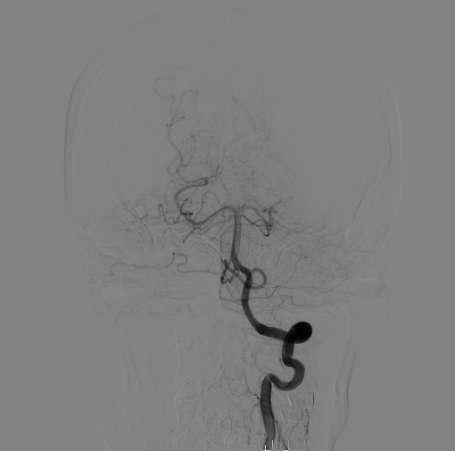

右侧颈总造影:右侧大脑中动脉瘤

右侧大脑中动脉瘤,瘤颈处发出颞支,颈宽3.79mm,瘤高3.51mm,远近端载瘤动脉直径分别为2.43mm、2.52mm。